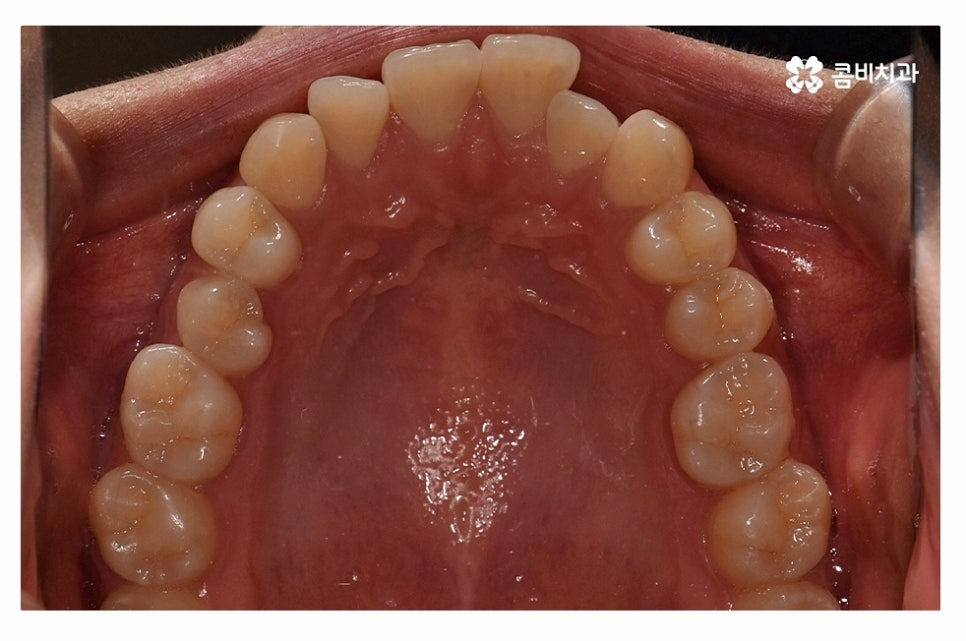

오늘 보여드릴 사례도 덧니교정이 비발치로 진행이 된 사례이며

치아의 이동 공간과 치아 상태, 골격, 얼굴형 등을

종합적으로 판단할 때 비발치로도 진행이 가능했던 사례라고 할 수 있어요.

덧니를 개선하려면 환자분들에 따라 골격부터 치아 구조 등을

정확히 파악해야 하며 치열이 이동하면서 바뀌게 되는 교합이나

얼굴 변화에 대해서도 종합적으로 예측하고 치료할 필요가 있는데요.